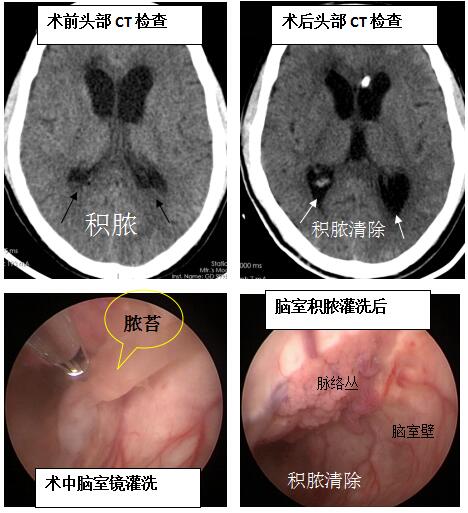

入院时直接进了ICU,当时患者为深昏迷状态,需要呼吸机辅助呼吸,脑脊液检验大量白细胞并引流管内为脓性脑脊液,检查结果显示:双侧脑室大量积脓。

神经外十科邓心情医生详细告知家属患者的病情与治疗方案,家属表示同意,在完善相关术前检查后,为患者实施脑室镜下脑室积脓灌洗术,利用脑室镜灌洗脑室积脓,冲洗出大量脓液,去除脑室壁脓苔,打通透明隔,术中单纯冲洗500毫升温盐水20袋,直至最后液体清亮。术后脑脊液白细胞正常,检查结果提示脑室积脓缓解。